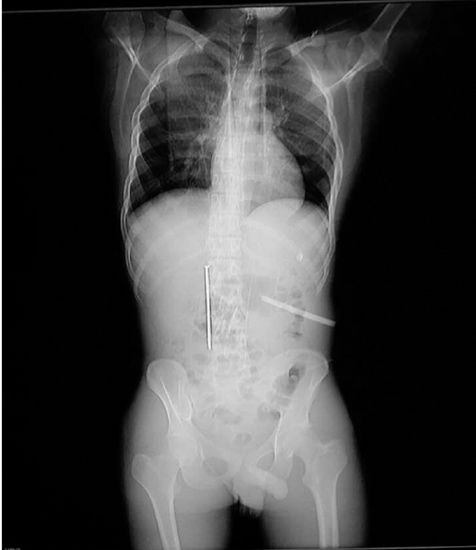

上图:影像显示出小龚腹中有异物。

室友吓了一跳,也来不及细问,赶紧把他送到李惠利医院,拍片忙了一圈,结果出来了:小龚的十二指肠有一段异物,另一段异物已经穿破胃壁,抵达腹腔,贴在腹壁上。

看到片子后,给他做检查的普外科副主任季晓春都有点傻了。